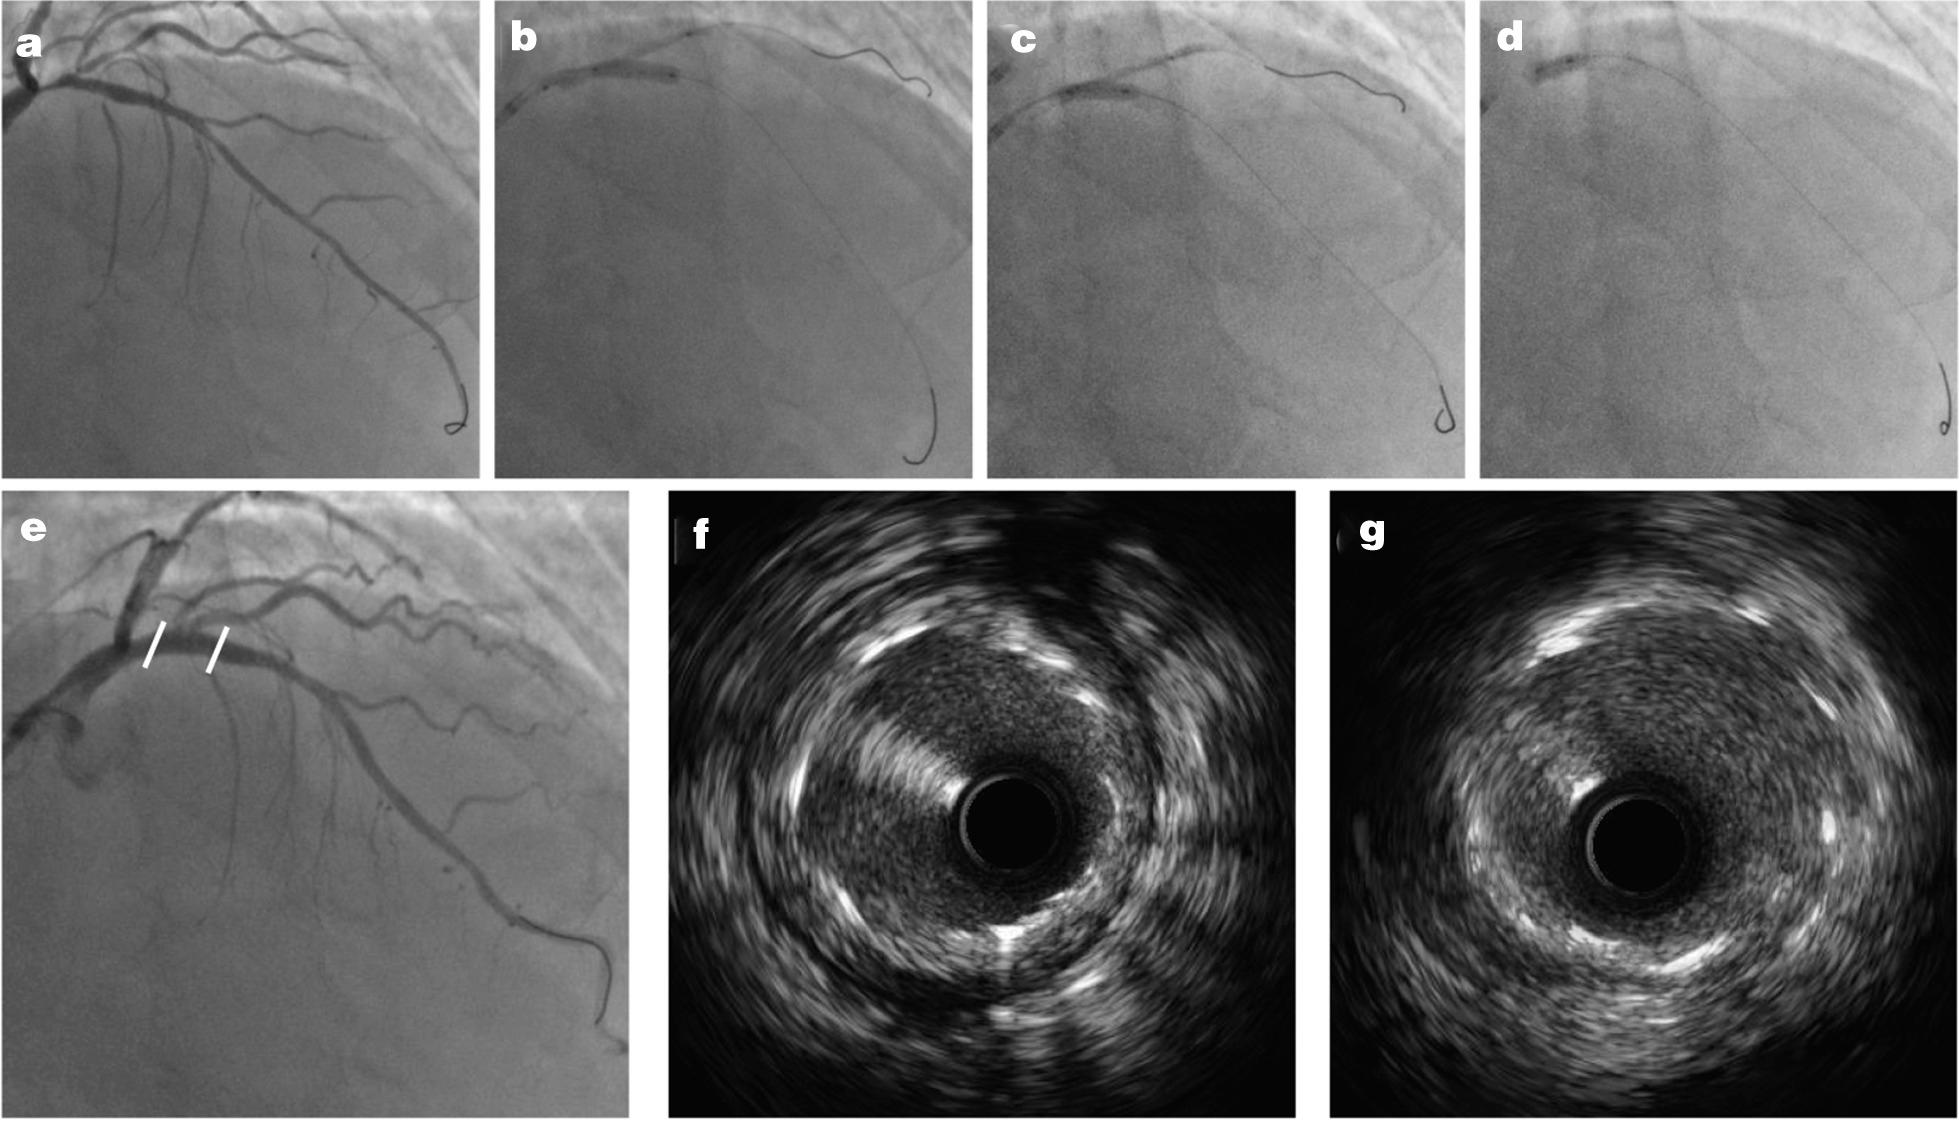

The jailed balloon technique is widely used for coronary bifurcation lesions, but a residual risk of SB occlusion remains, necessitating SB rewiring and further interventions, including balloon inflation or stenting, which may result in failure and SB loss. This study introduced a novel modified technique of small side branch (SB) protection, namely, double kissing inflation outside the stent (DKo) technique, for coronary bifurcations without the need for SB rewiring.

We performed the DKo technique in consecutive patients in our center from 1/2019 to 12/2019. The procedure was as follows. We inserted a guide wire into both branches followed by proper preparation. The SB balloon was simultaneously inflated with main vessel (MV) stenting. The SB balloon remained in situ until it was kissing inflated with postdilation of the bifurcation core, which is different from traditional strategies. The proximal optimization technique was performed with a short noncompliant balloon strictly not exceeding the bifurcation. Rates of SB loss and in-hospital outcomes were evaluated.

The technique was successfully performed in all 117 enrolled patients without any rewiring or SB loss. The mean lesion lengths of the MV and SB were 38.3 ± 19.9 mm and 11.7 ± 7.1 mm, respectively. On average, 1.5 ± 0.6 stents were used per patient, while the mean pressure of the SB balloon was 7.4 ± 3.1 atm. DKo achieved excellent procedural success in the proximal and distal MVs: increased minimal lumen diameter (0.64 ± 0.58 mm to 3.05 ± 0.38 mm, p < 0.001; 0.57 ± 0.63 mm to 2.67 ± 0.35 mm, p < 0.001) and low residual stenosis (11.4 ± 3.4%; 7.2 ± 4.6%). DKo secured the patency of the SB without any rewiring and improved the SB stenosis with minimal lumen diameter (0.59 ± 0.48 mm to 1.20 ± 0.42 mm, p < 0.001) and stenosis (71.9 ± 19.4% to 42.2 ± 14.0%, p < 0.001). No MACE was noted in the hospital.